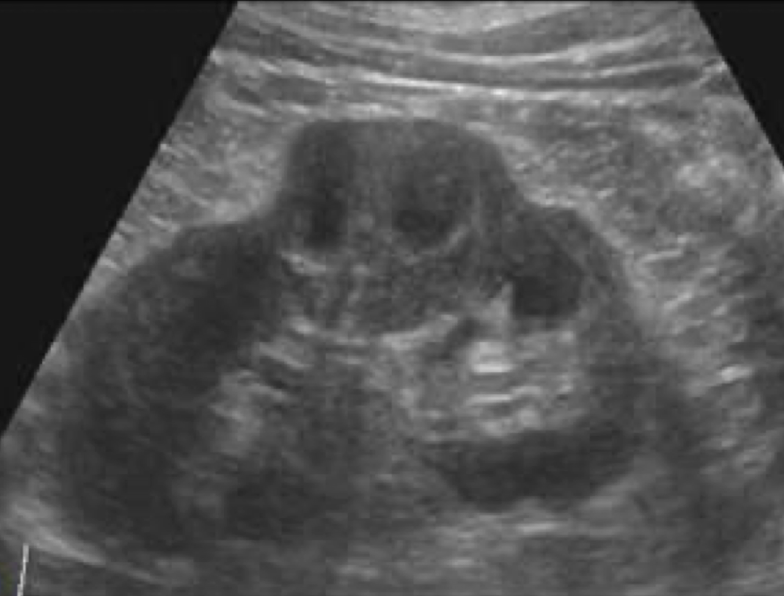

SONO: autosomal recessive polycystic kidney disease (ARPKD)

enlarged echogenic (cortex and medulla) kidneys with microscopic or small cysts

lack corticomedullary differentiation (can’t tell difference between cortex and medulla)